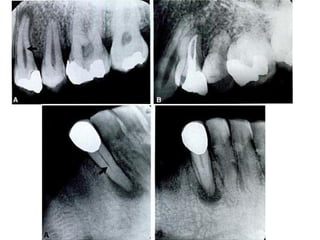

OVEREXTENDED preparation undermining enamel walls. The crown is

badly gouged owing to failure to observe pulp recession in the radiograph